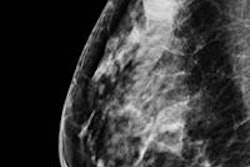

Women older than age 55 who are diagnosed with low-risk, localized early-stage breast cancer may be able to forego radiotherapy following breast conservation surgery, according to an Italian study presented at the recent American Society of Breast Surgeons' annual meeting in Chicago.

Patients enrolled in the trial had a tumor 2.5 cm or smaller that was a unifocal infiltrating carcinoma of any grade or receptor status. Nodal involvement could not exceed three nodes. The patients did not have any extensive intraductal component or extensive peritumoral vascular invasion. None of the patients had any prior history of cancer, with the exception of basal cell carcinoma skin cancer or in situ carcinoma of the cervix.